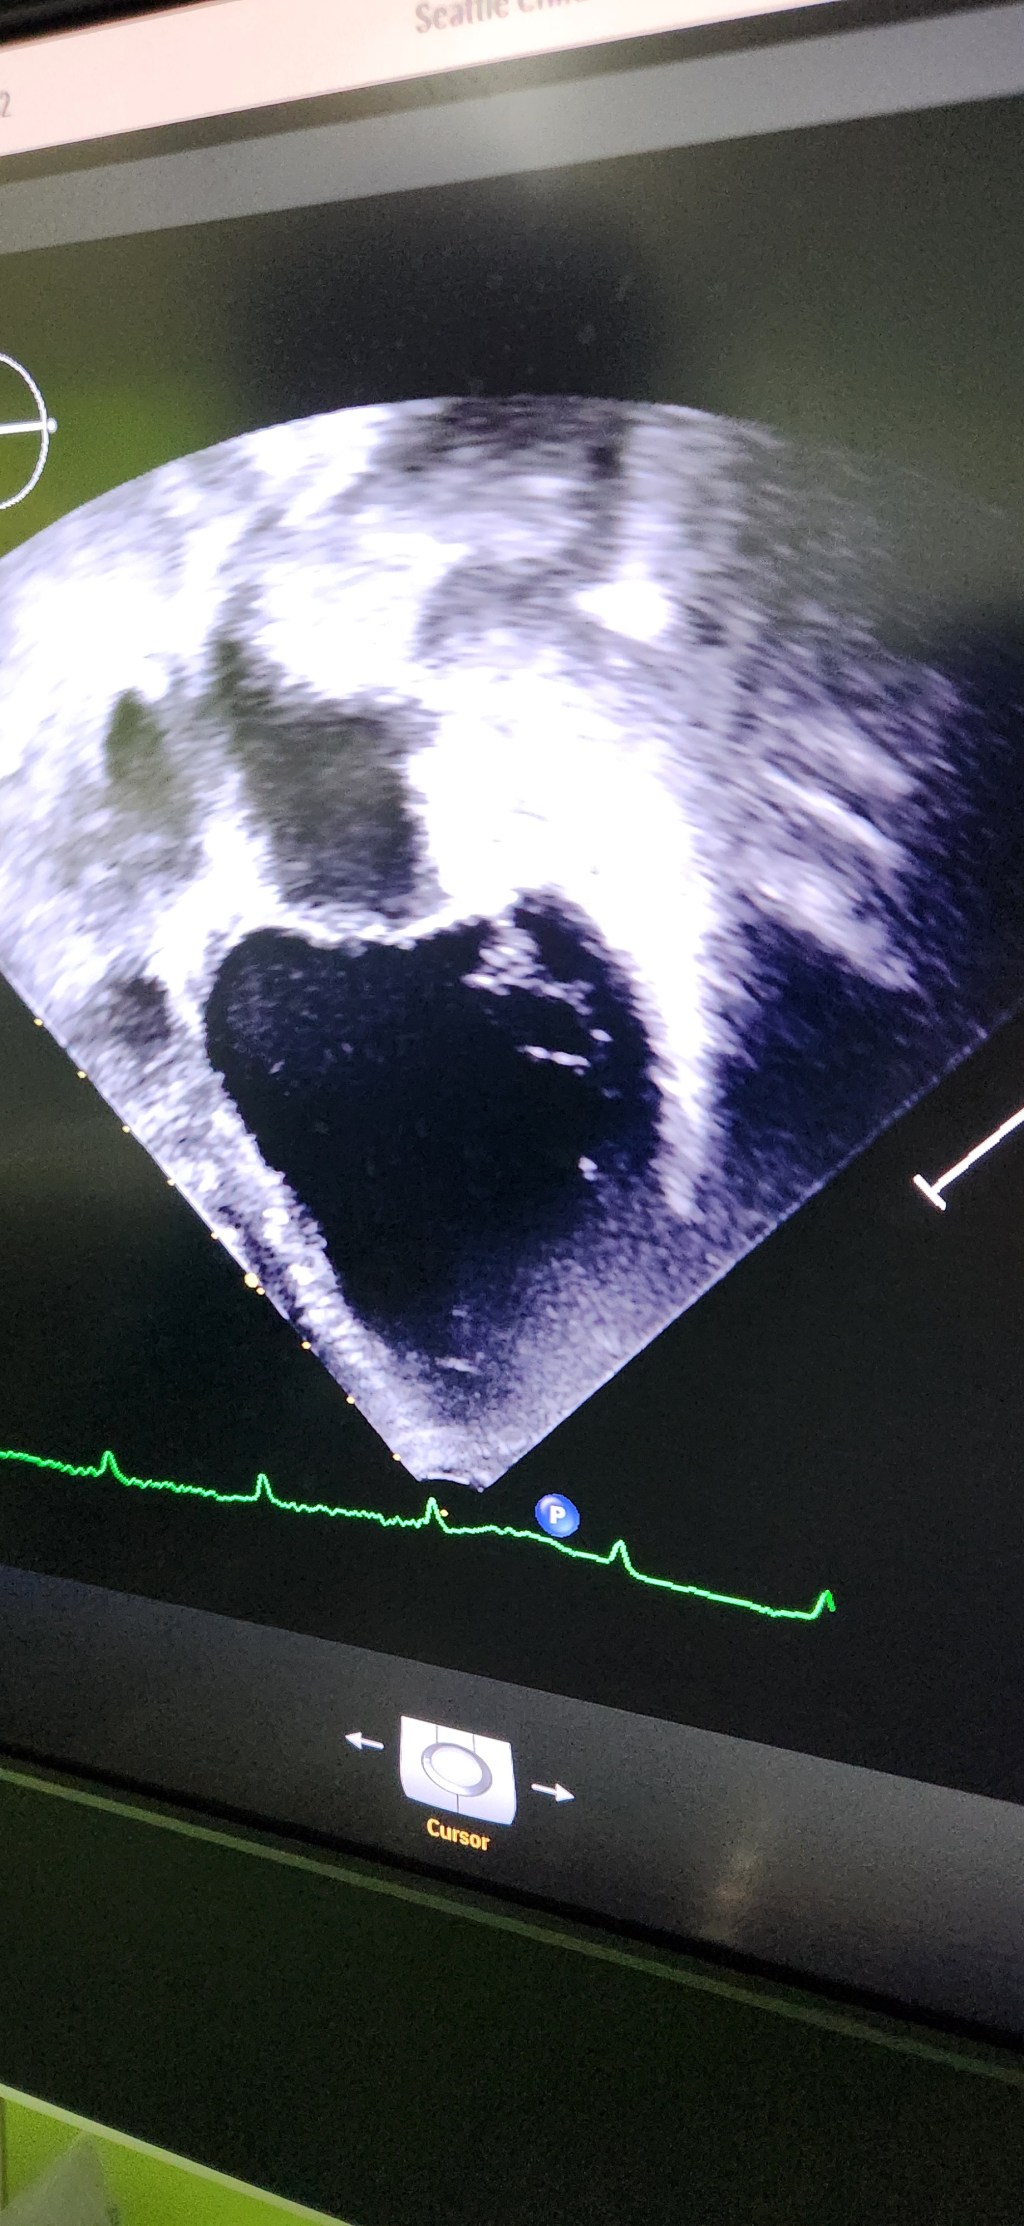

Now that graduation week has passed, the urgency for Katja has kicked in. She’s become much more tired/crabby this week. Her skin is now a constant molted blue/grey and she is definitely not herself.